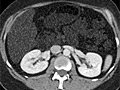

Computed Tomography (CT) Scan of the Body

A computed tomography (CT) scan uses X-rays to make detailed pictures of structures inside of the body.

A CT scan can be used to study all parts of your body, such as the chest, belly, pelvis, or an arm or leg. It can take pictures of body organs, such as the liver, pancreas, intestines, kidneys, bladder, adrenal glands, lungs, and heart. It also can study blood vessels, bones, and the spinal cord.